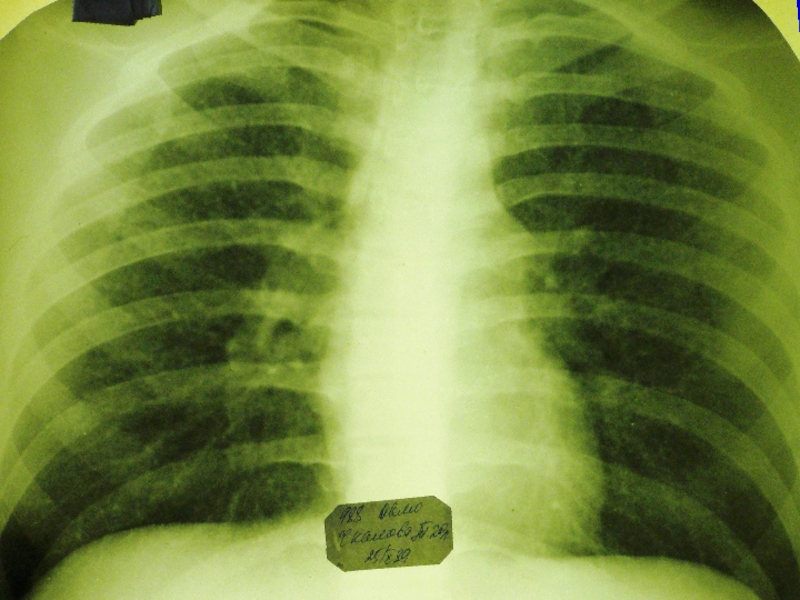

Рентгенологически симметрично в обоих легких, преимущественно в верхних и

средних отделах, обнаруживаются в одних случаях однотипные средние, в других

– крупные очаги.

При крупноочаговых процессах определяются очаги до 1 см, округлой или неправильной формы без резких очертаний, в верхних отделах могут обнаруживаться отдельные или множественные тонкостенные (штампованные) каверны, которые в части случаев выявляются только при томографическом исследовании.

В редких случаях лимфогенного диссеминированного туберкулеза очаги располагаются в средних отделах на фоне выраженной сетчатой и линейной тяжистости. Корни легких и при гематогенной и лимфогенной диссеминации обычно нерезко расширены.